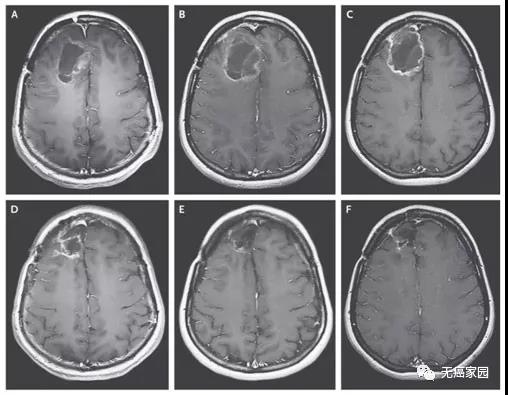

图示分泌BiTE靶向EGFR的CART-EGFRvIII细胞,让小鼠脑内的肿瘤在3周之内显著缩小甚至完全消失